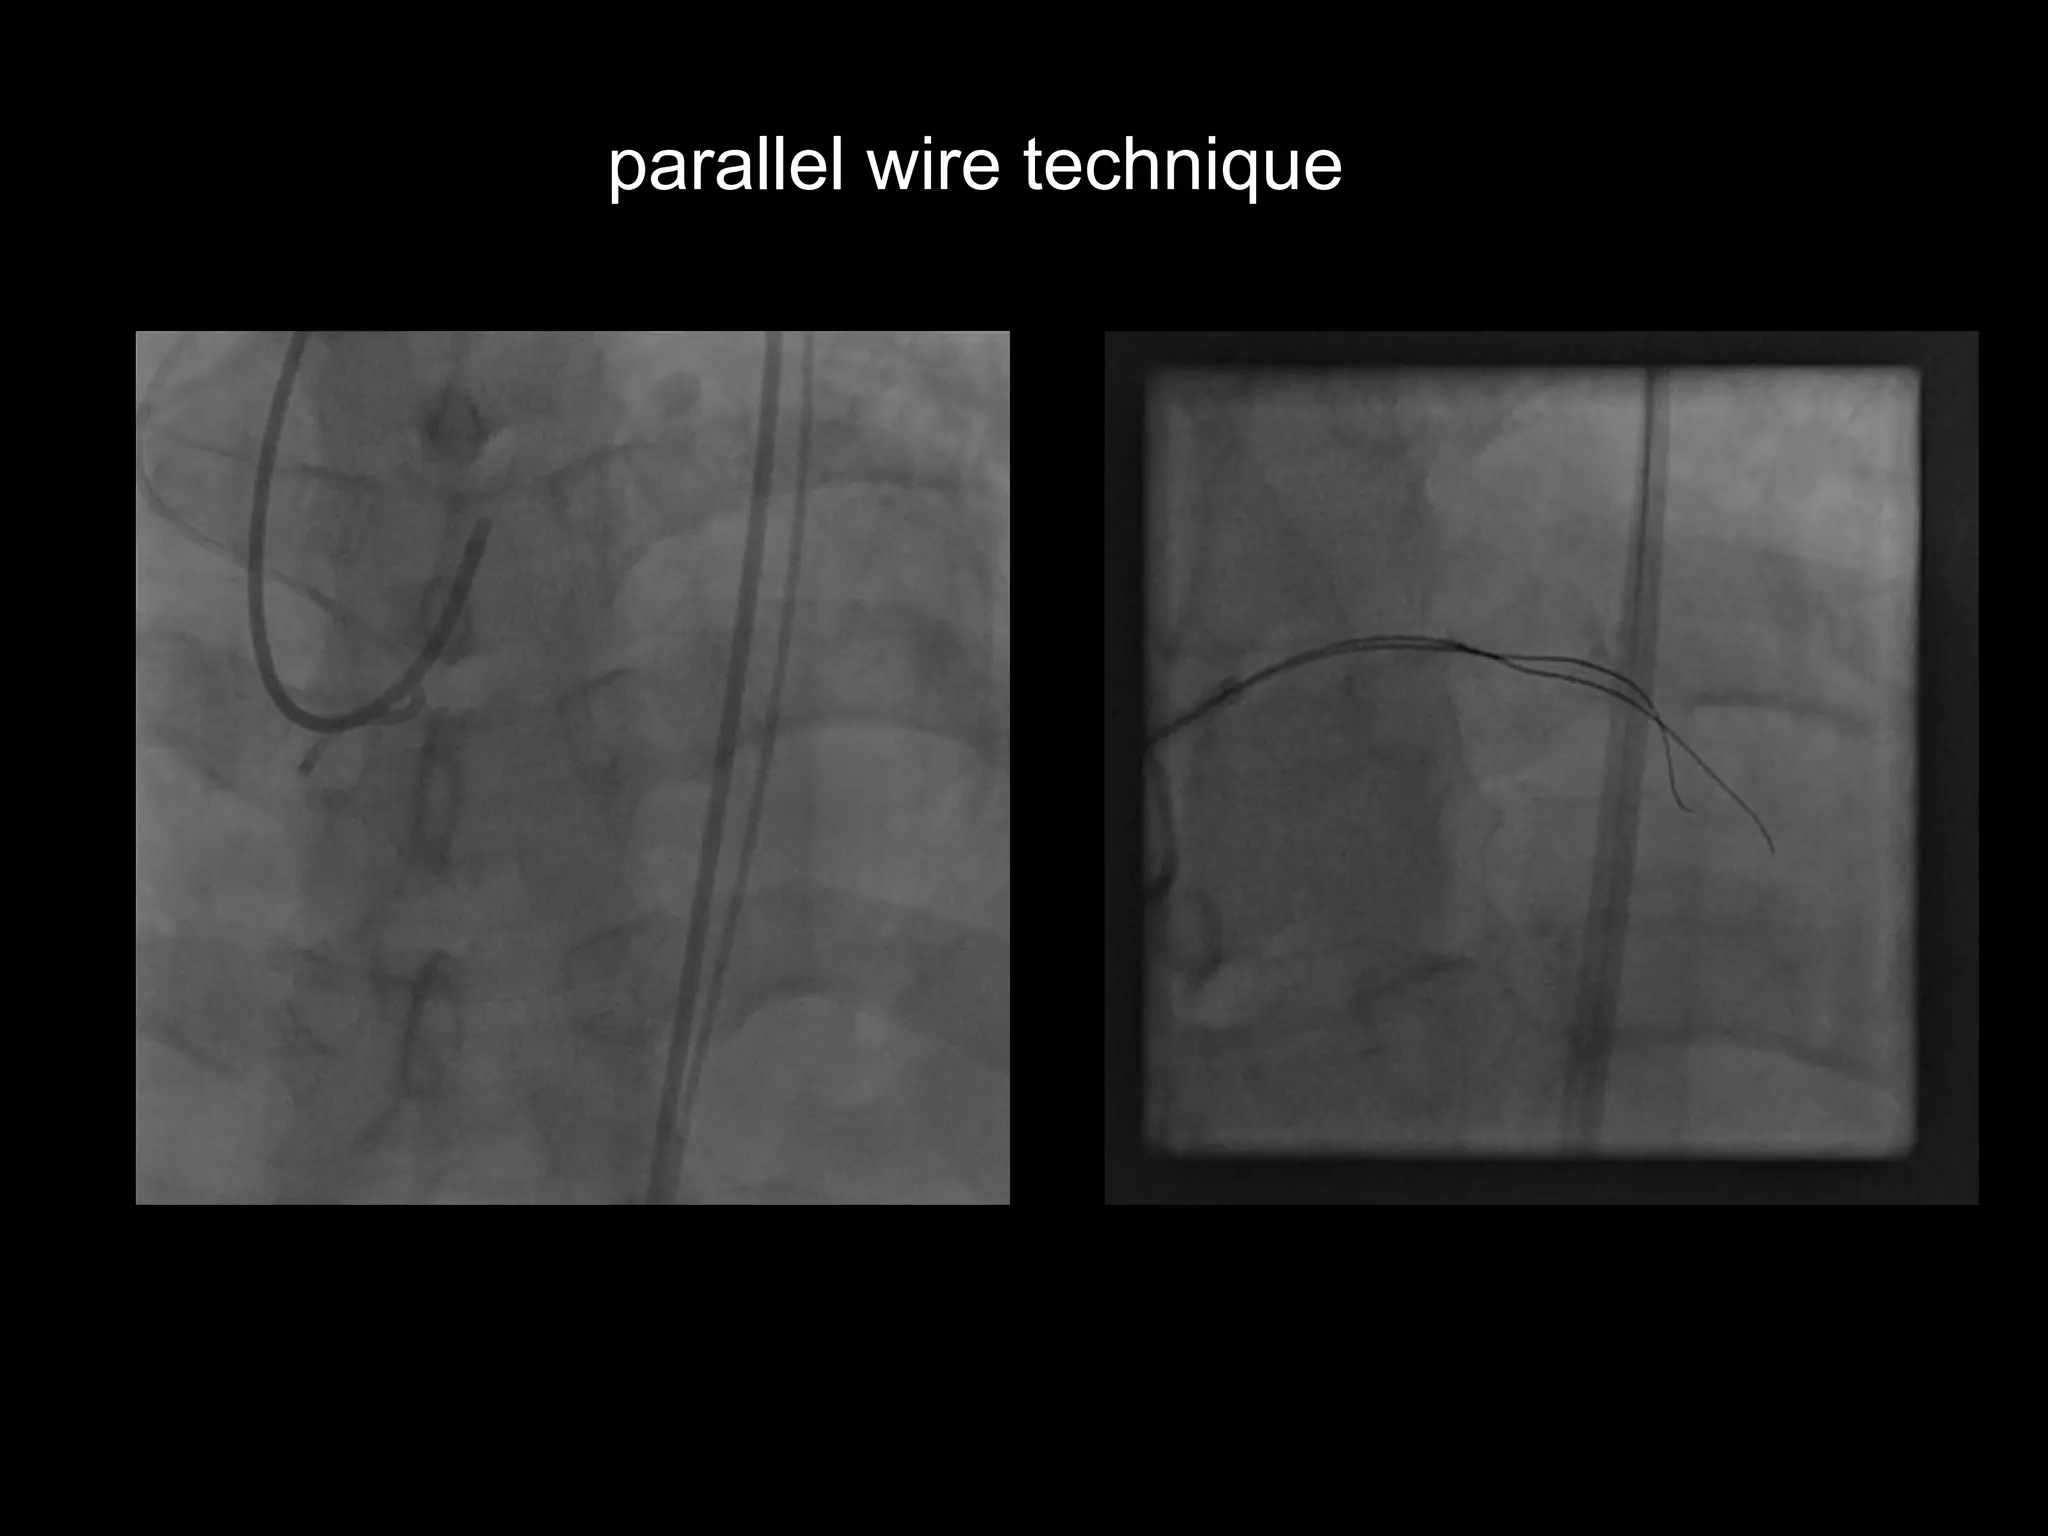

parallel wire technique